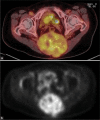

Figure 10:

PET-CT scan. An increase in SUV (SUVmax 6.9) was demonstrated.

Figure 15:

a and b PET-CT scan. An increase in uptake of the sacral tumour (SUVmax 6.7).